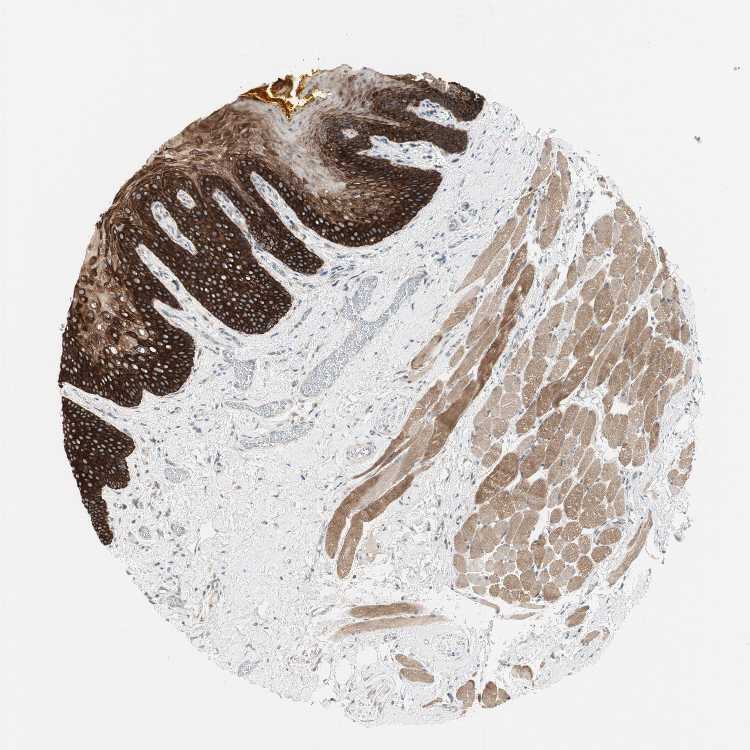

TISSUE PRIMARY DATA ORAL MUCOSA Show tissue menu

ORAL MUCOSA - Antibody stainingi

Antibody staining in the annotated cell types in the current human tissue is reported as not detected, low, medium, or high, based on conventional immunohistochemistry profiling in selected tissues. This score is based on the combination of the staining intensity and fraction of stained cells.

Each image is clickable and will lead to virtual microscopy that enables deeper exploration of all samples and also displays staining intensity scores, fraction scores and subcellular localization as well as patient and tissue information for each sample.

Antibody HPA006009

Squamous epithelial cells High